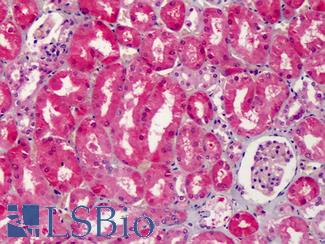

Anti-COX-2 antibody IHC of human kidney. Immunohistochemistry of formalin-fixed, paraffin-embedded tissue after heat-induced antigen retrieval. Antibody LS-B1608 concentration 5 ug/ml.

Cyclooxygenase 2 (COX-2 / PTGS2)